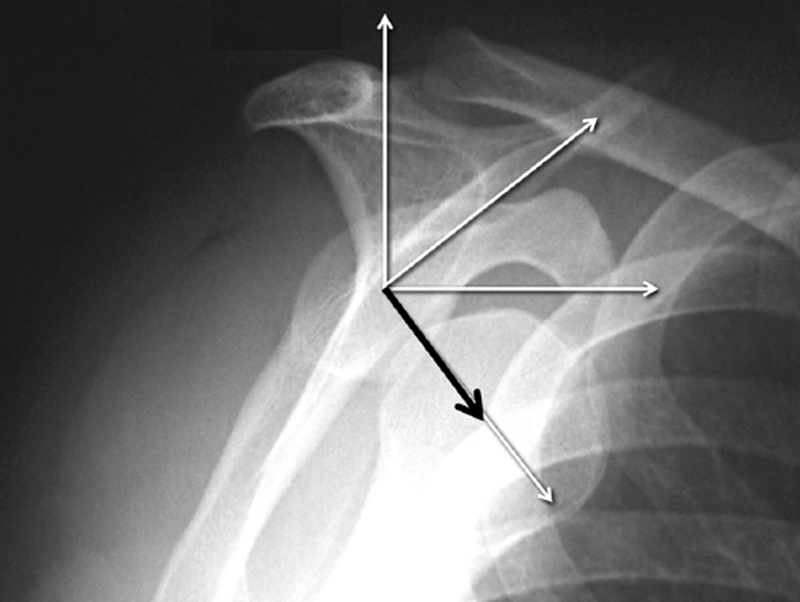

肩关节脱位大都是前下脱位,但相对于肩胛盂来说是往前方脱位。

在4:30钟位逐步形成前下部骨缺损。